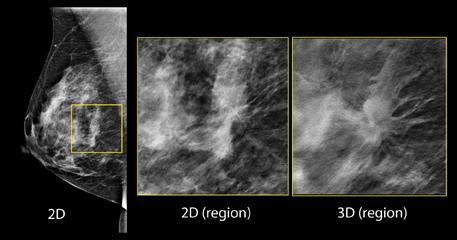

Despite decades of progress in breast imaging, one challenge continues to test even the most skilled radiologists ...

Despite its small size, Gritman Medical Center, a 25-bed hospital in Moscow, Idaho, has a reputation for thinking big, especially when it comes to women’s health. That’s why in May 2014 the hospital became the very first facility in the region to install a Hologic 3D mammography system and began to offer breast tomosynthesis services to its patients. The addition of the Hologic system represents a significant capital investment for the hospital, especially since they decided from the start not to charge women an additional fee for 3D mammograms. “3D was not a financial decision, it was a decision based upon what is the right thing to do for the women we serve,” noted Christin Reisenauer, M.D., director of imaging at the hospital’s Patricia J. Kempthorne Women’s Imaging Center. “We knew we were missing breast cancers with 2D mammography, cancers potentially visible with breast tomosynthesis, and that just wasn’t fair to the women of our area.”

Multiple studies and products were presented at the 2014 Radiological Society of North America (RSNA) conference in December about emerging technologies in breast imaging, with a focus on how they will affect women who have dense breasts. Most researchers have been comparing the utility of mammography screening versus tomosynthesis.